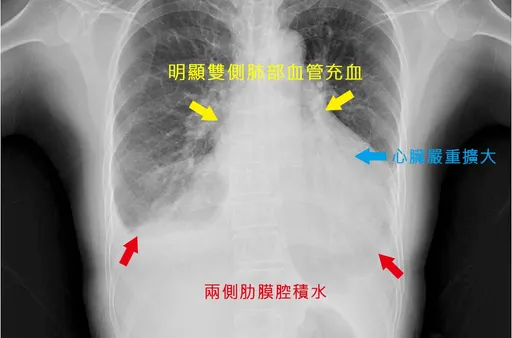

...是因為心臟功能不好,多餘的體液就會滯留在胸腔,導致肺部積水,出現呼氣不順、容易咳嗽的情況。 熱門新...